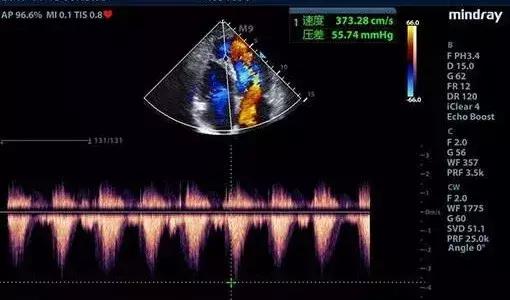

彩超具有彩色多普勒血流显像功能,可以显示病变区域的血管解剖结构、血流方向、血流速度和血流状态改变,可以明显提高对疾病的鉴别能力,提高诊断的准确性。

心血管腔疾病超声诊断

包括常规超声心动图检查、颈部动静脉、腹腔动静脉、肾动脉、四肢大动脉及深静脉系的形态结构、血流动力学检查。

超声心动图检查系将超声探头置于胸壁、食管内,对立体的心脏进行无数切面扫描、综合分析心脏各结构的位置、形态、活动与血流特点,从而获得心血管疾病的解剖、生理、病理及血流动力学诊断资料。近年来食管内超声进一步拓宽其应用范围,大大提高了诊断敏感性与特异性。

1、先天性心血管结构异常:如房缺、室缺、法乐氏三、四联症、动脉导管未闭、心内膜垫缺损、大动脉转位、肺静脉畸形引流、先天性瓣叶发育畸形等。

2、心瓣膜病变:对心瓣膜狭窄、关闭不全、瓣叶钙化、脱垂、穿孔、瓣环钙化、赘生物附着、瓣叶发育畸形等病变均能作出明确诊断。

3、应用于高血压心脏病、肺源性心脏病、甲亢性心脏病、心肌病、主动脉夹层动脉瘤、主动脉窦瘤及破裂、冠心病、心脏肿瘤(粘液瘤、横纹肌瘤)及心腔内血栓形成。

4、颈动脉、腹主动脉、肾动脉、四肢大动脉的内膜病变、斑块形成或狭窄等病变;头颈、腹腔及四肢静脉的血栓形成、扩张、畸形等病变。